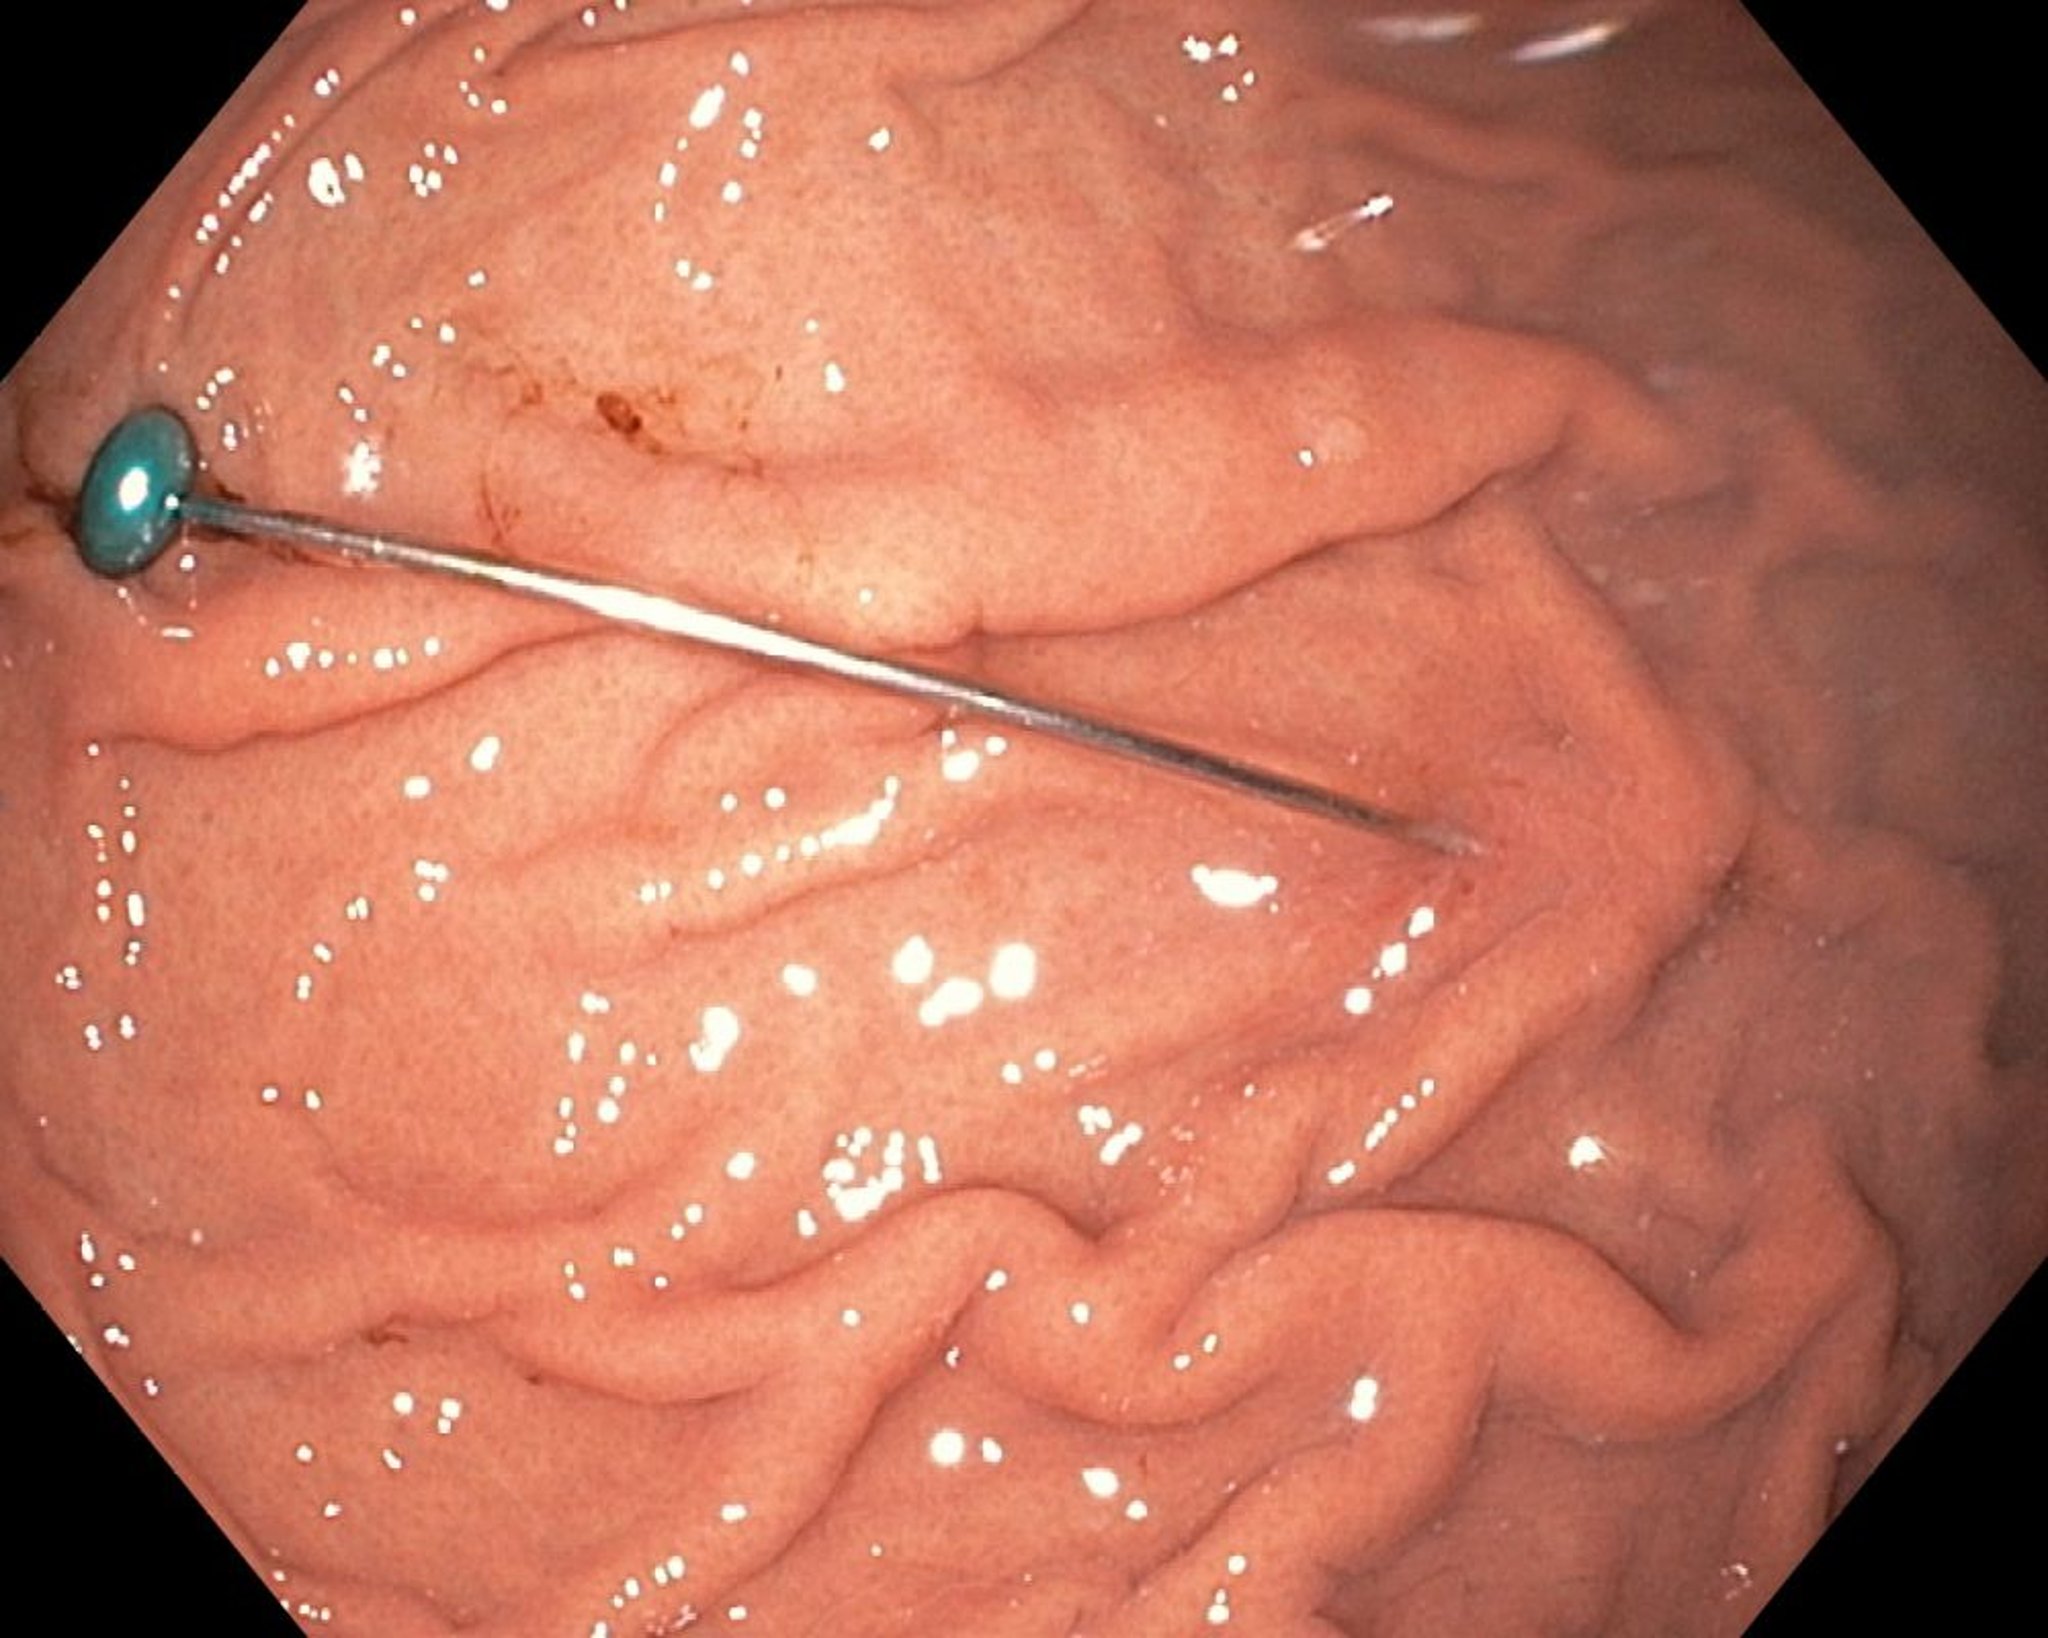

جسم أجنبي حاد في المعدة (تنظير داخلي)

تُظهر هذه الصورة جسمًا حادًا في المعدة.

Image provided by Uday Shankar, MD.